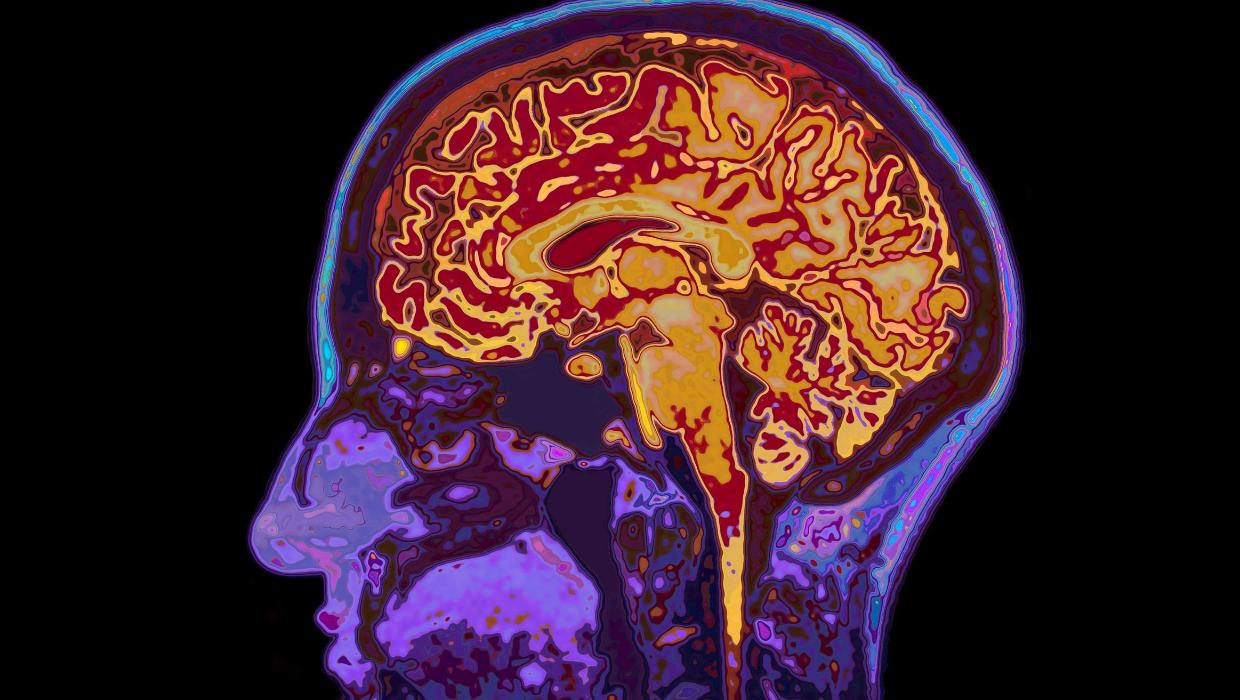

A recent study conducted by the University of Cambridge reveals that human brain development continues into the early thirties, specifically until the age of 32. This groundbreaking research identifies five major epochs of brain development, marking significant turning points in an individual’s life.

The findings suggest that cognitive and emotional maturation occurs in distinct phases, with four critical junctures that shape how individuals think and behave. The study, published in March 2024, challenges the traditional view that brain development is largely complete by the late teens.

Researchers categorized brain development into five key epochs: early childhood, late childhood, adolescence, young adulthood, and finally, early adulthood. Each epoch is characterized by unique neurological changes that influence learning, social behavior, and decision-making.

The first epoch, early childhood, lays the groundwork for cognitive abilities, followed by late childhood, which further enhances these skills. Adolescence, often viewed as a tumultuous time for emotional development, transitions into young adulthood, where individuals refine their decision-making processes. The final epoch, early adulthood, extends to 32, where the brain achieves a more stable and mature state.